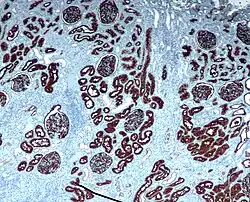

Immunohistochemical staining is widely used in the diagnosis of abnormal cells such as those found in cancerous tumors. In some cancer cells certain tumor antigens are expressed which make it possible to detect. Immunohistochemistry is also widely used in basic research, to understand the distribution and localization of biomarkers and differentially expressed proteins in different parts of a biological tissue.[4]

Reporter molecules vary based on the nature of the detection method, the most common being chromogenic and fluorescence detection. In chromogenic immunohistochemistry an antibody is conjugated to an enzyme, such as alkaline phosphate and horseradish peroxidase, that can catalyze a color-producing reaction in the presence of a chromogenic substrate like 3,3'-diaminobenzidine (DAB).[5] The colored product can be analyzed with an ordinary light microscope.[13] In immunofluorescence the antibody is tagged to a fluorophore, such as fluorescein isothiocyanate, tetramethylrhodamine isothiocyanate, aminomethyl Coumarin acetate or Cyanine5. Synthetic fluorochromes from Alexa Fluors is also commonly used.[13][14] The fluorochromes can be visualized by a fluorescence or confocal microscope.[13]

Immunohistochemistry is an excellent detection technique and has the tremendous advantage of being able to show exactly where a given protein is located within the tissue examined. It is also an effective way to examine the tissues. This has made it a widely used technique in neuroscience, enabling researchers to examine protein expression within specific brain structures. Its major disadvantage is that, unlike immunoblotting techniques where staining is checked against a molecular weight ladder, it is impossible to show in immunohistochemistry that the staining corresponds with the protein of interest. For this reason, primary antibodies must be well-validated in a Western Blot or similar procedure. The technique is even more widely used in diagnostic surgical pathology for immunophenotyping tumors (e.g. immunostaining for e-cadherin to differentiate between ductal carcinoma in situ (stains positive) and lobular carcinoma in situ (does not stain positive)[19]). More recently, immunohistochemical techniques have been useful in differential diagnoses of multiple forms of salivary gland, head, and neck carcinomas.[20]